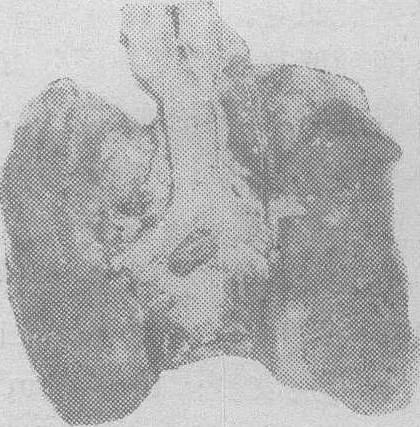

窒息死者肺膜下斑点状出血(塔雕斑) (3) 浆膜和粘膜下点状出血。最常见于肺膜和心外膜下,特别是肺下叶或叶间的肺膜下; 心脏则多见于膈面,近房室交界处。数量多少不一,有时较大,也可很小,很少,要用放大镜才看得清楚在胸腺、甲状腺、颌下腺的包膜下,有时在喉粘膜、脑的蛛网膜、小肠粘膜、睾丸等处均可发生。这些出血点最早由Tardieu于1879年描述,故亦称塔雕斑(Tardieu's spots)。 (4) 肺气肿或水肿。在剧烈的呼吸困难期,在胸腔负压的作用下,肺脏可以扩大,肺泡膨胀,尤其在肺的前缘可形成局灶性肺气肿,甚者并发肺泡破裂,导致间质性肺气肿。肺部高度郁血,可导致肺水肿,窒息过程迁延较久者,肺水肿更明显,可在呼吸道形成浅红色泡沫。 上述各种尸体征象,其发生的程度在各个窒息尸体轻重不一,在各类型机械窒息也有所不同。而且,许多非窒息死者的尸体(特别是各种急死尸体),也可能具有其中一种或多种改变,因此,这些改变都不是特异性的,不能据此肯定死亡原因,必须结合其他各种情况分析判定。 机械性窒息的鉴定 除了对死者的个人识别,判断死亡时间等一般鉴定事项外,主要解决: ❶是否机械窒息死,属何种类型,是否为生前受机械性暴力引起的窒息死亡。 ❷尸体有无其它暴力痕迹及其与死因和案件的关系。 ❸判别自杀、他杀或灾害死。 ☚ 微波损伤 缢死 ☛ 00007780 |